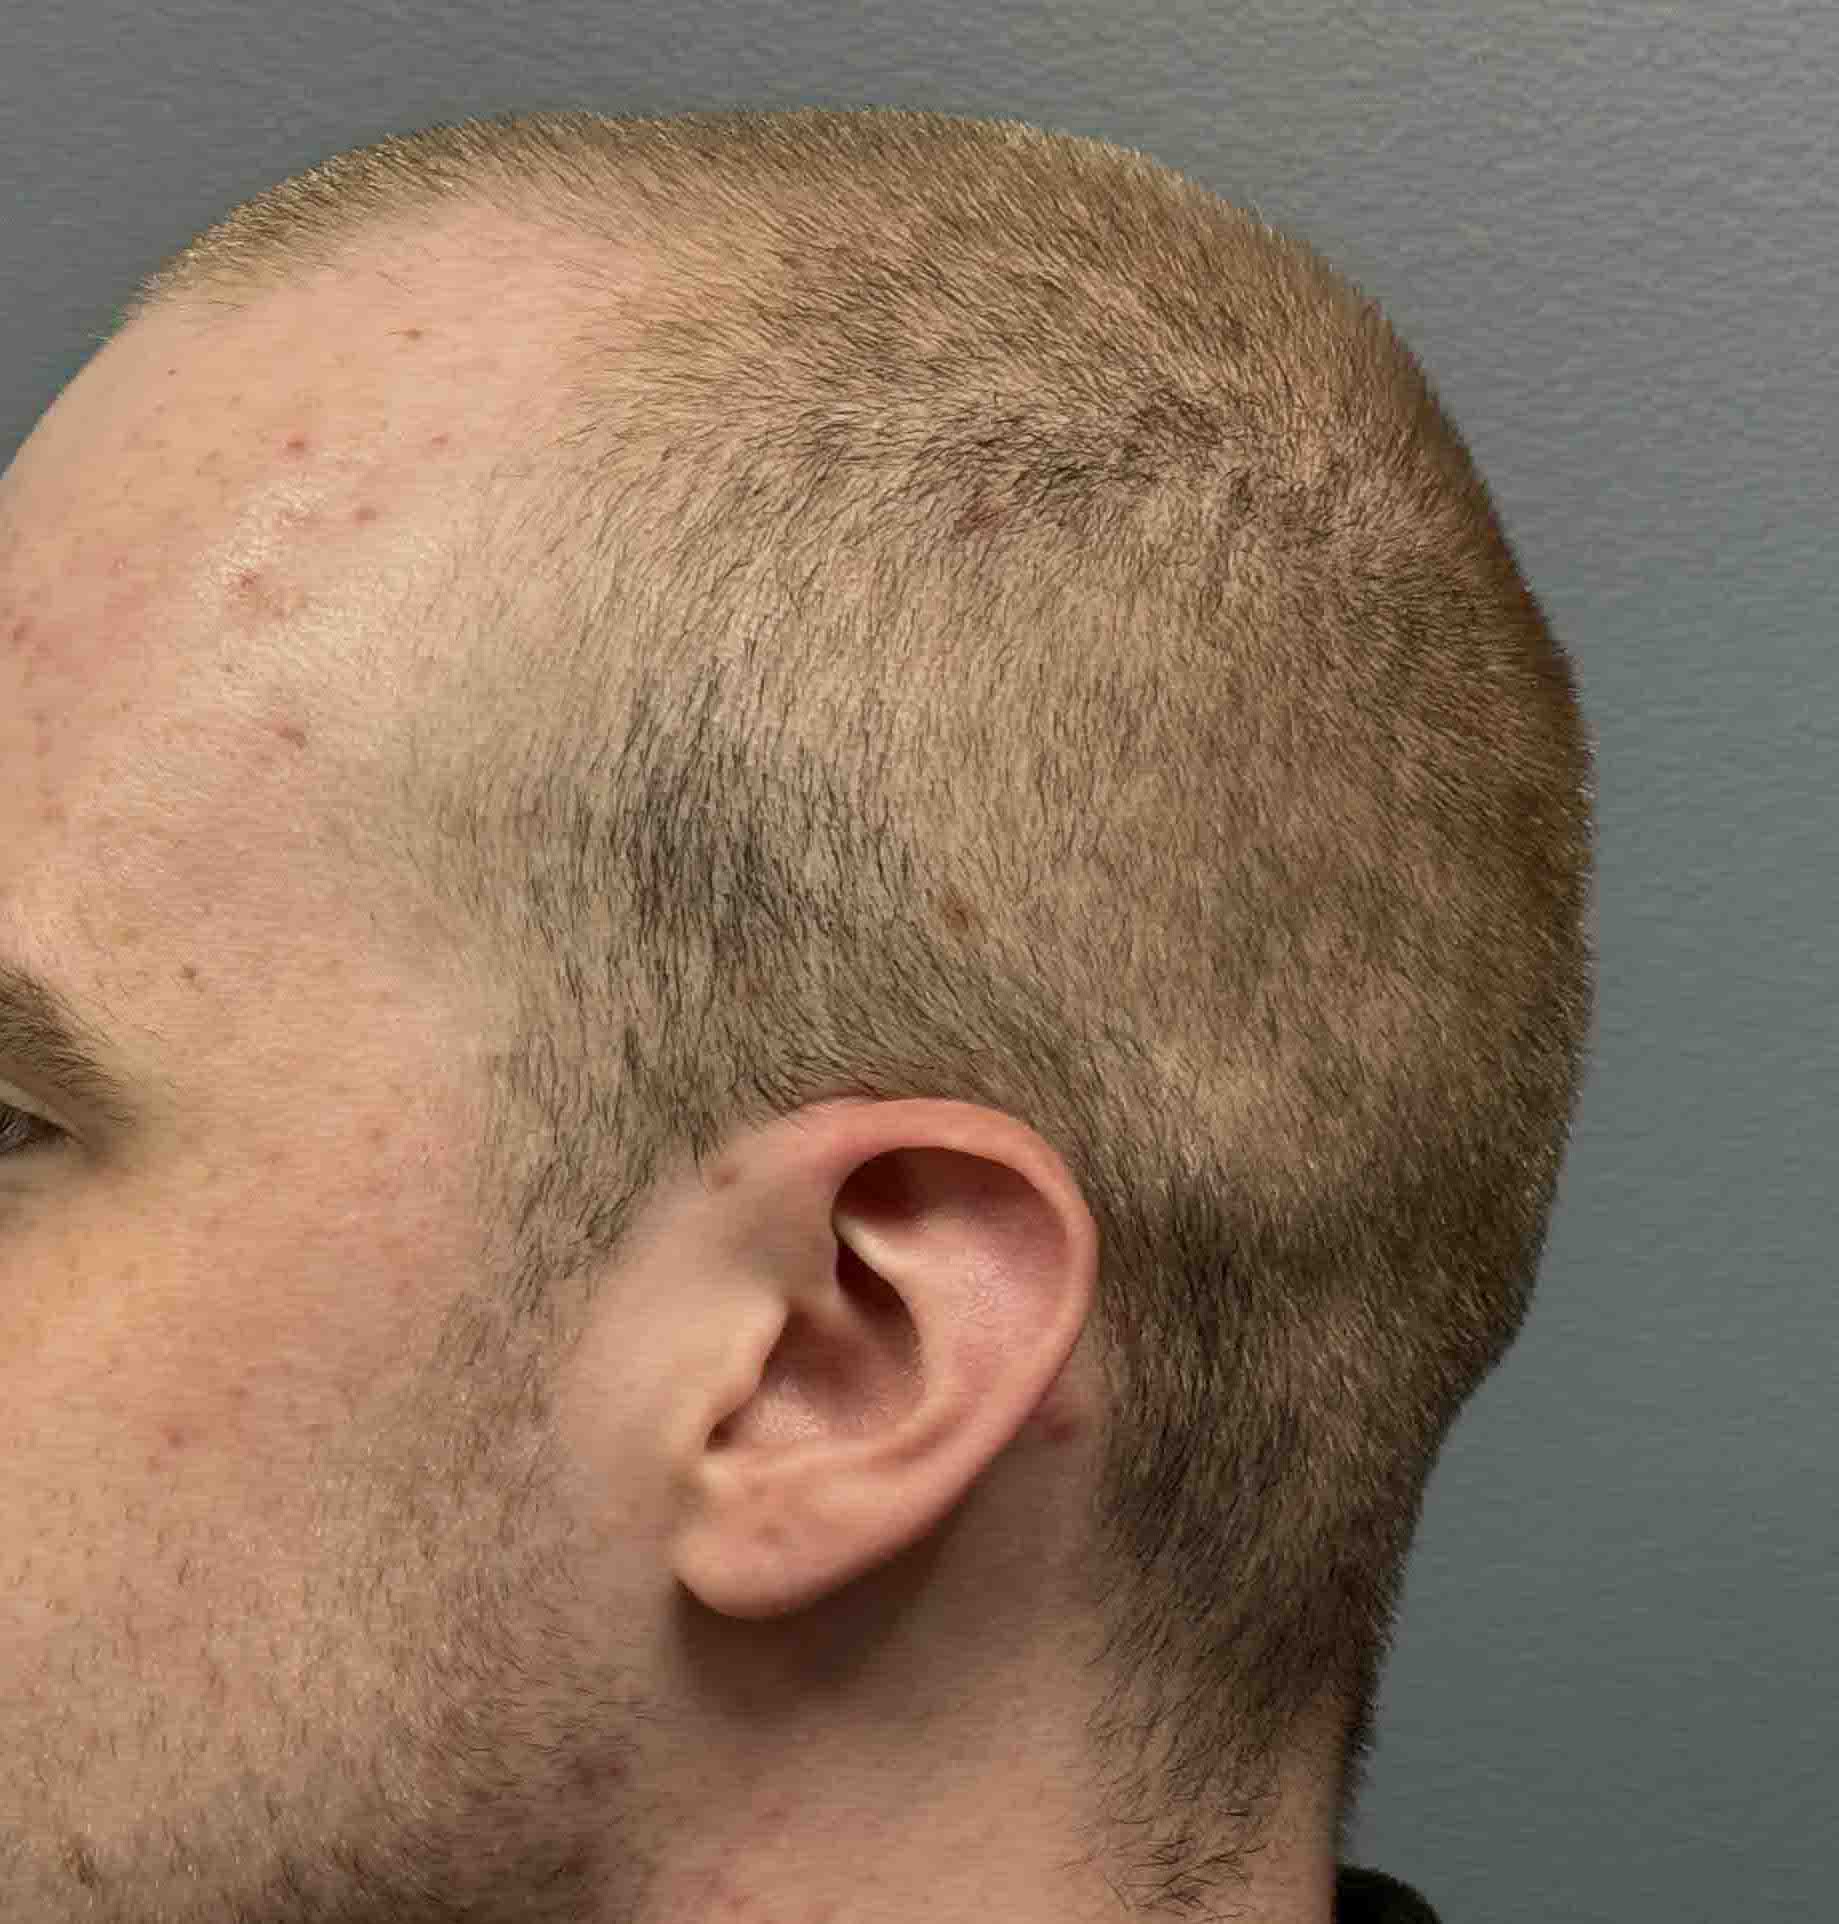

Desire for reshaping of an asymmetric flat back of the head in a shaved head male.

A combined back of the head reshaping procedure was done with a custom skull implant, sagittal ridge reduction and a right temporal muscle reduction.

Desire for reshaping of an asymmetric flat back of the head in a shaved head male.

A combined back of the head reshaping procedure was done with a custom skull implant, sagittal ridge reduction and a right temporal muscle reduction.